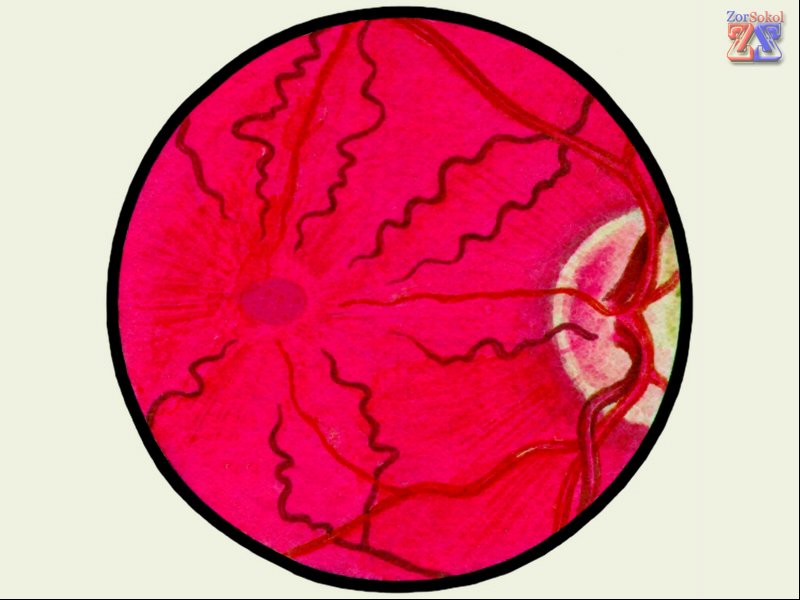

Ангиопатия представляет собой изменение структуры сосудов сетчатки глаза, которые могут сужаться, расширяться или искривляться. Это состояние обычно не рассматривается как отдельное заболевание, а выступает в роли симптома других патологий. К таким заболеваниям относятся гипертония, гипотония, диабет, атеросклероз и другие. В некоторых случаях ангиопатические изменения могут возникать во время беременности или после травм.

Гипертоническая. Эта форма ангиопатии может возникать во время беременности или у пожилых людей. На начальных стадиях человек может не замечать никаких симптомов, однако врач при осмотре может обнаружить, что сосуды сетчатки изогнуты и сужены. В запущенных случаях это может привести к серьезным последствиям, таким как кровоизлияния (иногда обширные), накопление жидкости, а также расслоение и отслоение тканей сетчатой оболочки.

Гипотоническая. При этой форме сосуды становятся расширенными и сильно изогнутыми, их тонус снижен, что затрудняет нормальное кровообращение и может способствовать образованию тромбов. Пациенты могут ощущать пульсацию вен в глазах.

Диабетическая. При сахарном диабете страдает вся сосудистая система, включая сосуды сетчатки. Это приводит к замедлению кровообращения, а просветы сосудов могут забиваться мукополисахаридами, что вызывает их сужение и возможную закупорку. В результате возникает гипоксия тканей глаза, что может привести к серьезным осложнениям.

Травматическая и юношеская. Травматическая форма возникает из-за травм головы, глаз или шейного отдела позвоночника, которые приводят к сжатию сосудов. Юношеская форма чаще всего наблюдается у детей, и причины ее возникновения зачастую остаются неизвестными.